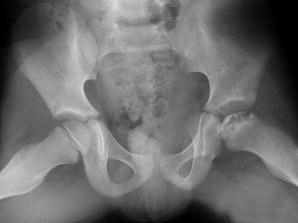

问题 男,6岁,髋痛、跛行,请结合CR检查,选出最可能的诊断 ( )

选项 A、骨囊肿 B、软骨肉瘤 C、股骨头骨骺缺血坏死 D、骨肉瘤 E、髋关节结核

答案 C